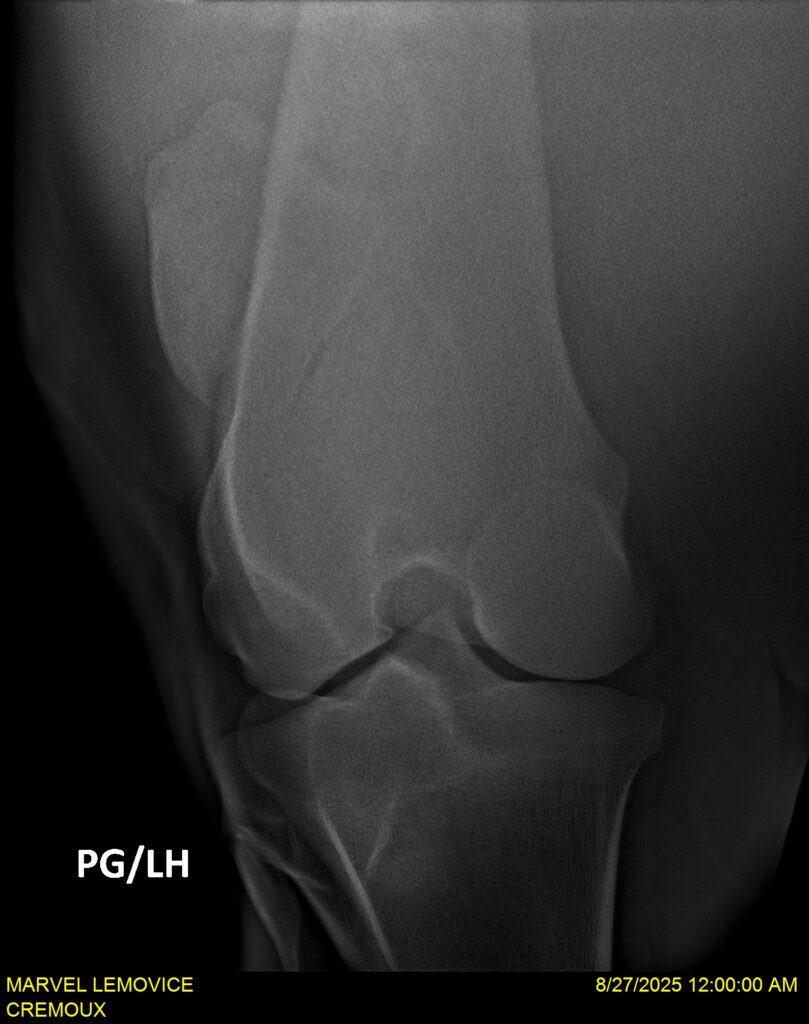

MARVEL LEMOVICE, hongre, Selle Français prend 4 ans en 2026. POPSTAR LOZONAIS x ROSIRE sur une excellente souche maternelle de l’élevage PLATIERE. Débourré aux trois allures et mise en route à l’obstacle. Super modèle avec du cadre et de la force, cheval respectueux avec des moyens. Très agréable au quotidien. Transport OK, maréchalerie OK, santé RAS, Bilan 20 clichés radios + clinique OK.

RADIOS ET CLINIQUE